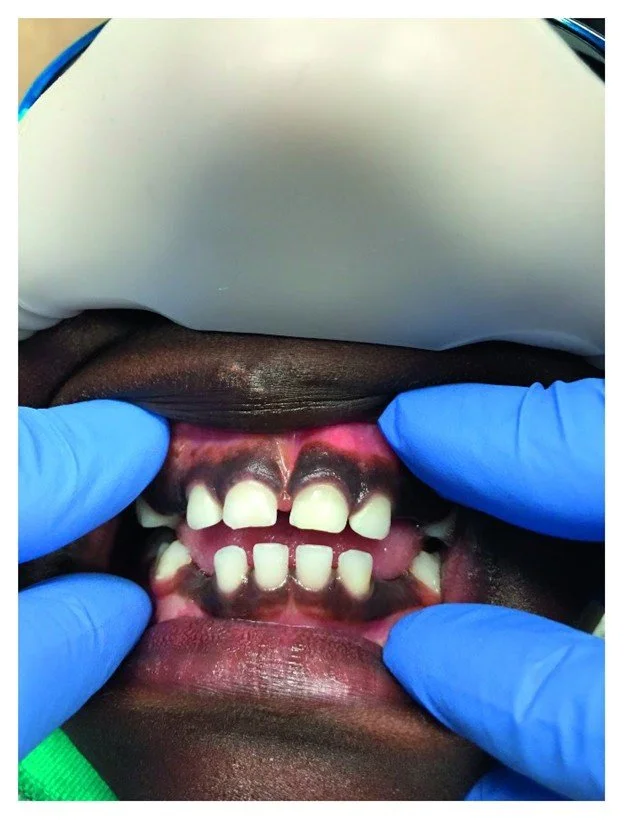

Upon evaluation, it was noted that the patient was missing the maxillary and mandibular right and left primary canines (Figure 1). Following the clinical evaluation, two bitewings in addition to maxillary and mandibular anterior periapical radiographs were obtained to evaluate proximal tooth surfaces for caries, investigate canine areas, and rule out other pathology.

Figure 1

An intraoral photo of the 4-year-old male patient shows the missing maxillary and mandibular right and left primary canines.